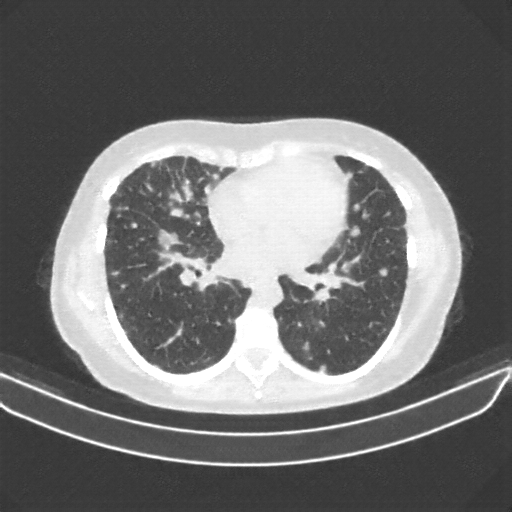

Targeted Slice 70 - Lung Window Analysis (Generated vs Real Venous)

0.728

Lung SSIM

109.0

Lung RMSE

48.5

Lung MAE

Average Lung Window Metrics Across All Slices (133 slices) - Generated vs Real Venous

0.727

Lung SSIM (Avg)

108.6

Lung RMSE (Avg)

46.1

Lung MAE (Avg)

Original VENOUS CT scan

Lung window (WL -600, WW 1500 β†’ Low βˆ’1350, High +150)